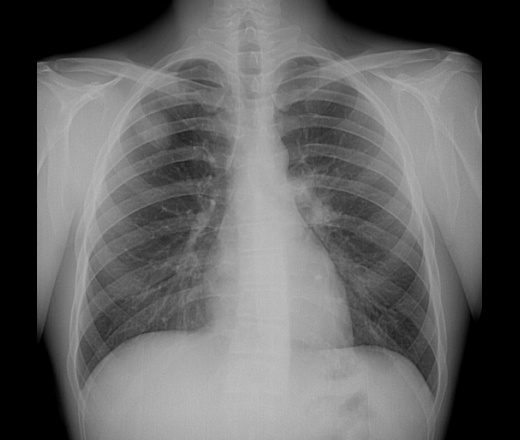

Рентген грудной клетки

Рентген грудной клетки помогает выявить проблемы с сердцем и легкими. Рентгенограмма грудной клетки слева в норме. На изображении справа показано образование в правом легком.

Рентген грудной клетки позволяет получить изображения сердца, легких, кровеносных сосудов, дыхательных путей, костей грудной клетки и позвоночника.

Рентген грудной клетки также может выявить жидкость в легких или вокруг них или воздух, окружающий легкое.